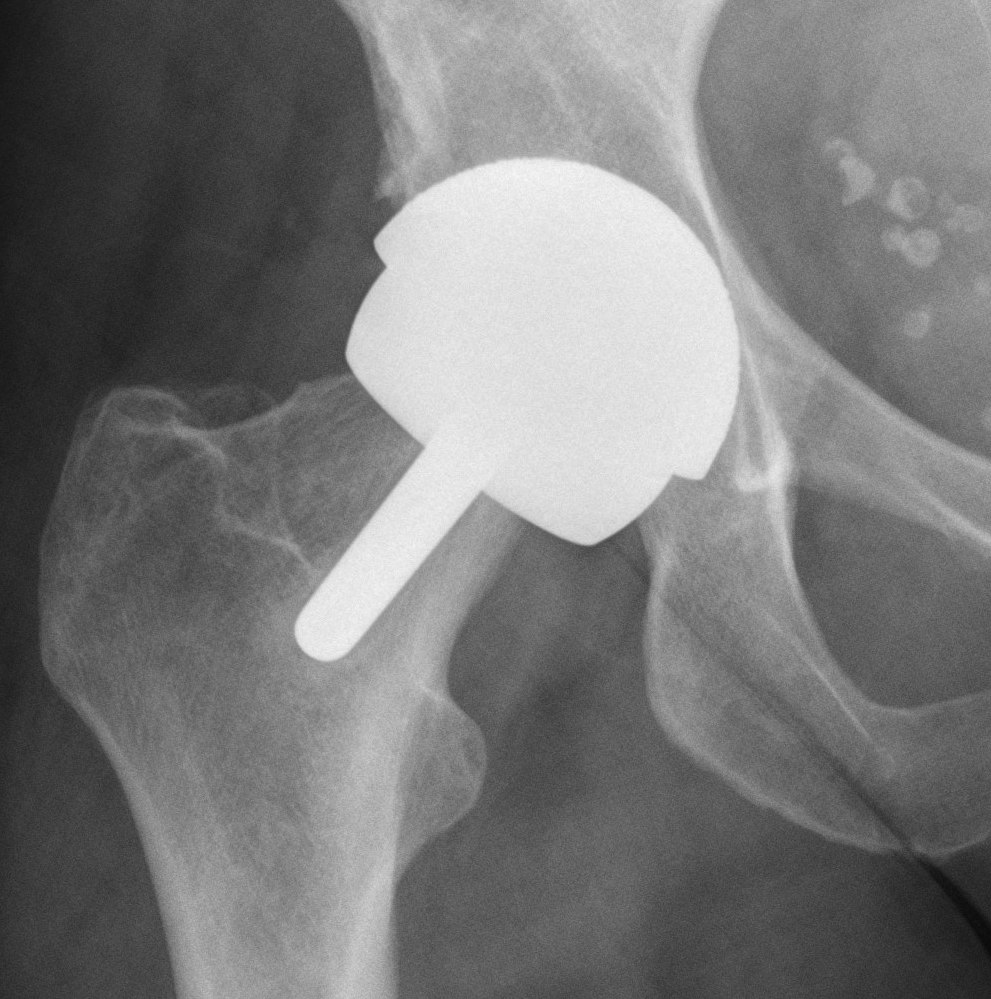

Femur

- removal of femoral head cartilage

- resurfacing with metal

- cemented / uncemented

Acetabulum

- standard technique

Bearing surface

- metal on metal

Relatively young man (40 - 50)

OA